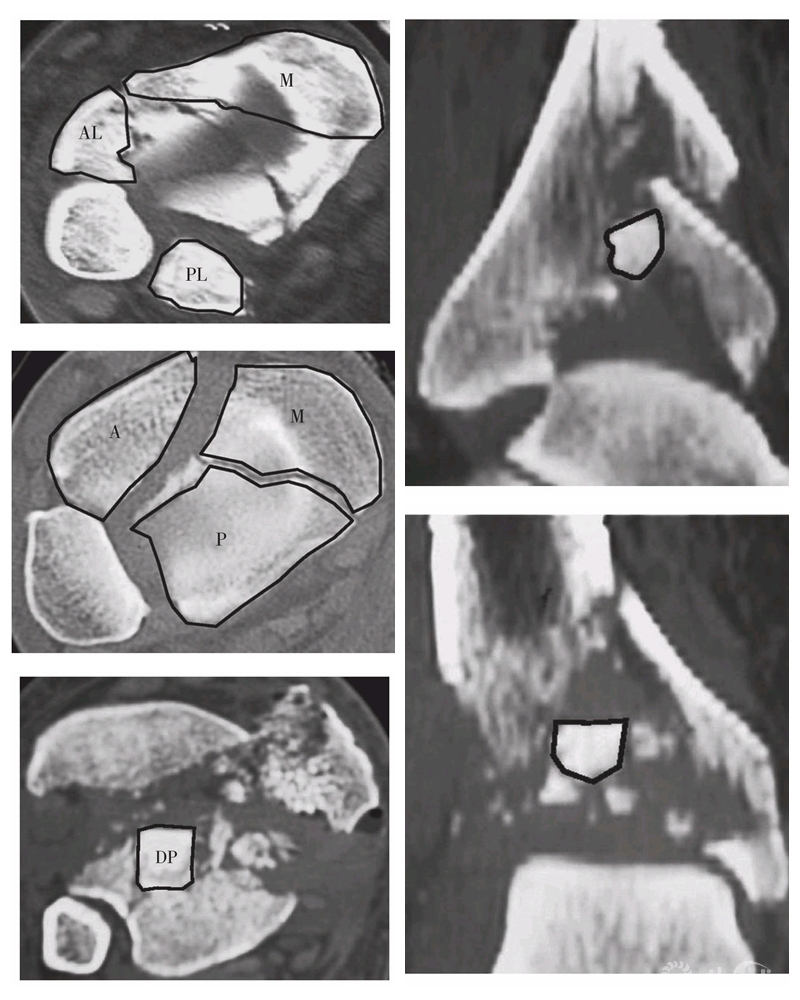

Pilon骨折主要骨折块

1.内侧骨块;2.前外侧Chaput骨块;3.后外侧Volkmann骨块;4.前侧骨块;5.后侧骨块;6.Die-punch骨块

Topliss等分析了126例Pilon骨折患者中的108张CT片,提出了累及关节的6个主要骨块为前侧、后侧、内侧、前外侧(Tillaux-Chaput)、后外侧(Volkmann)和冲床样(Die-punch)骨折块。同时,他们根据主要骨折线的方向把骨折分为两大类(6%无法辨认,5%为边缘性骨折)。主要骨折线前后方向位于矢状面占33%(图18-2-6),可分为纵向分裂型(SS)、倒V型(IV)和T型(T),纵向分裂型为相对较低能量下出现的单一骨折线,后两者为能量继续增加造成的结果;主要骨折线内外方向位于冠状面占56%(图18-2-7),可分分为横向分裂型(CS)、前侧分裂型(AS)、后侧分裂型(PS,后Pilon骨折)、V型(V)和Y型(Y),后两者也是相对较高能量损伤的结果。他们认为,矢状面骨折通常存在内翻成角,常发生于高能量损伤的年轻患者;冠状面骨折倾向于存在外翻成角,常发生于低能量损伤的老年患者。

Pilon骨折主要骨块CT表现

AL:前外侧骨块;M:内侧骨块;PL:后外侧骨块;A:前侧骨块;P:后侧骨块;DP:Die-punch骨块